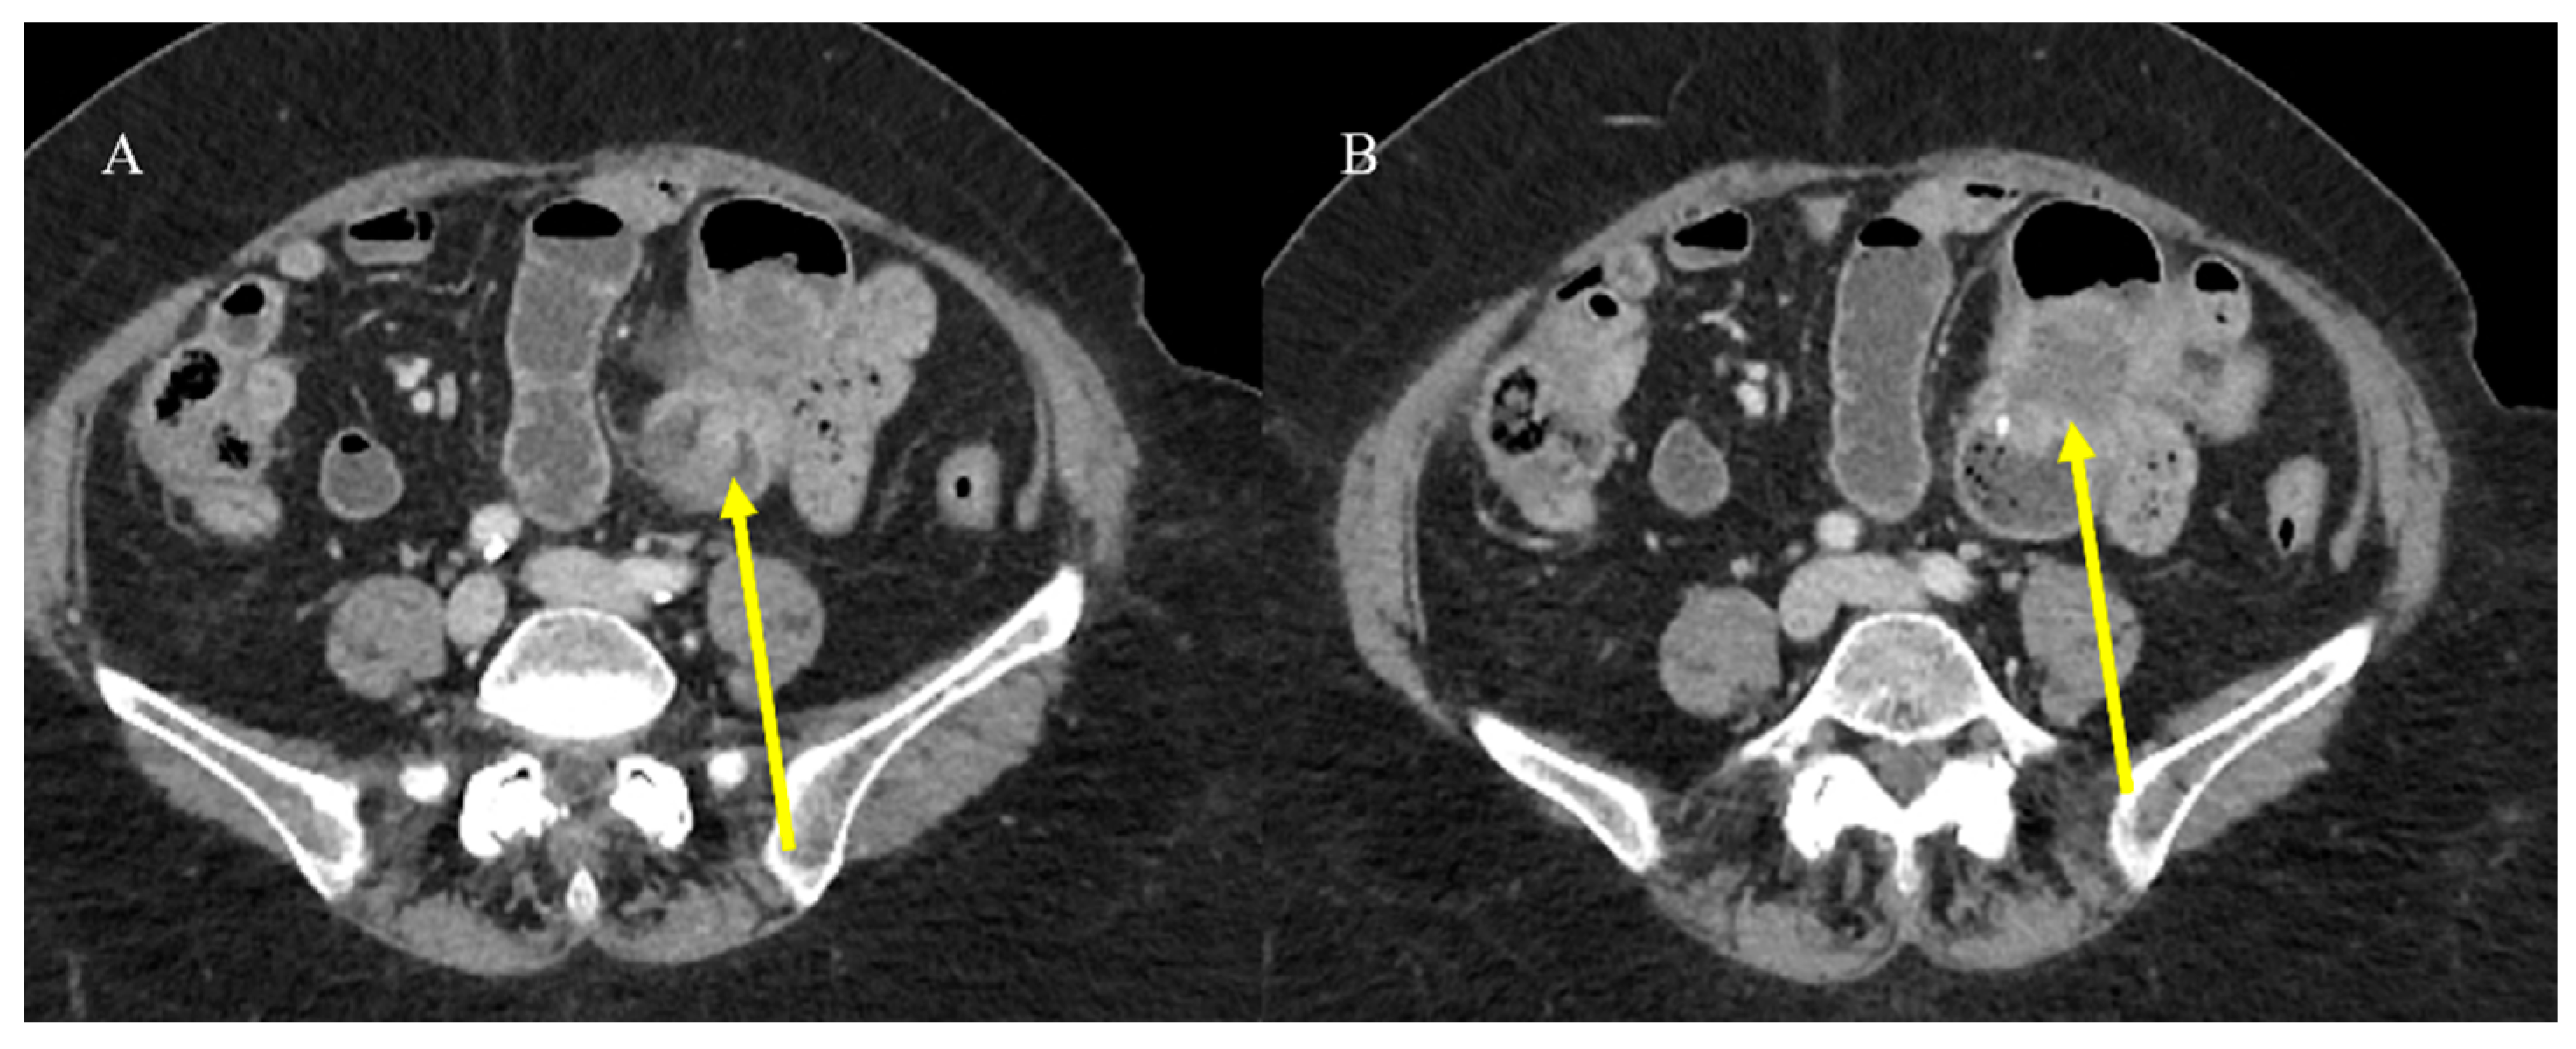

- Chao, T.C.; Chao, H.H.; Jan, Y.Y.; Chen, M.F. Perforation through small bowel malignant tumors. J. Gastrointest. Surg. 2005, 9, 430–435. [Google Scholar] [CrossRef] [PubMed]

- Mooghal, M.; Ahmad, A.; Safi, A.; Khan, W.; Ahmad, N. Impending perforation near ileocecal junction due to phytobezoar impaction and intraluminal polyp: A case report. J. Med. Case Rep. 2022, 16, 124. [Google Scholar] [CrossRef] [PubMed]

- Carney, B.W.; Khatri, G.; Shenoy-Bhangle, A.S. The role of imaging in gastrointestinal bleed. Cardiovasc. Diagn. Ther. 2019, 9 (Suppl. S1), S88. [Google Scholar] [CrossRef]

- Pouli, S.; Kozana, A.; Papakitsou, I.; Daskalogiannaki, M.; Raissaki, M. Gastrointestinal perforation: Clinical and MDCT clues for identification of aetiology. Insights Imaging 2020, 11, 31. [Google Scholar] [CrossRef]